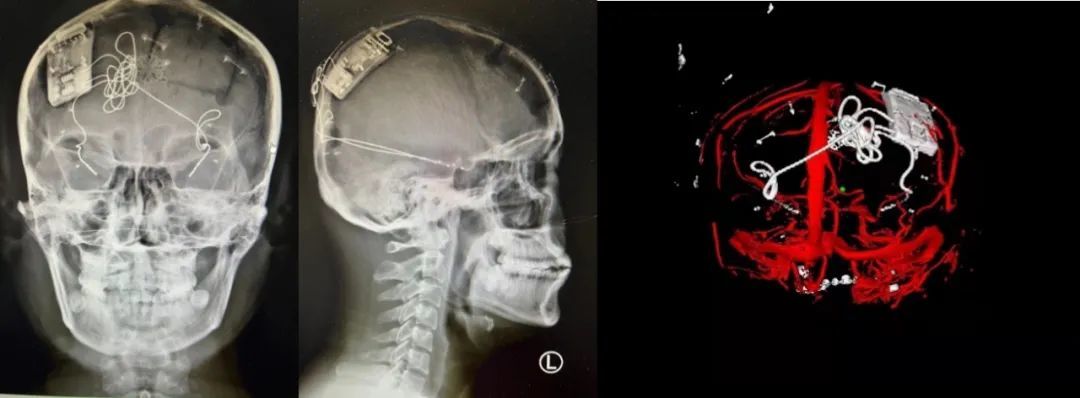

本次手術(shù)過(guò)程順利,術(shù)中刺激器各項(xiàng)指標(biāo)均工作正常,術(shù)后重建顯示電極位置精準(zhǔn),腦電信號(hào)清晰?;颊邽槟行?,入院后診斷為雙側(cè)顳葉癲癇,此類癲癇為開(kāi)顱手術(shù)的相對(duì)禁忌癥,在藥物無(wú)法控制的情況下,傳統(tǒng)治療效果欠佳 。

團(tuán)隊(duì)根據(jù)術(shù)前計(jì)劃,在手術(shù)機(jī)器人輔助下完成雙海馬長(zhǎng)軸電極及 IPG 植入,術(shù)后重建顯示電極位置精準(zhǔn),腦電信號(hào)清晰。術(shù)后第二天,患者即下床活動(dòng),身體狀況恢復(fù)良好。